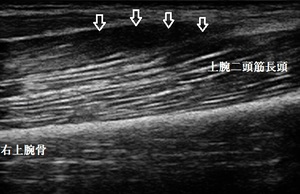

坂戸市若葉 肘(腕)の痛み 上腕二頭筋炎

右上腕遠位端 超音波長軸像 同部 4週後

坂戸市若葉 40代女性会社員。 肘(うで)の痛み、右上腕二頭筋炎。

当接骨院で超音波検査を実施したところ、右上腕二頭筋が腫れて炎症が起きている様子がみとめ

られました(左上画像の丸の中=腫れ、炎症=赤、橙、青色の点)。

画像右上は4週後の画像ですが、女性は仕事を休むことなく炎症症状が消失しました(矢印は腫れが

若干残存している状態)。

痛みは消失していますが、女性の希望で完全に腫れが引くまで治療を継続予定です。